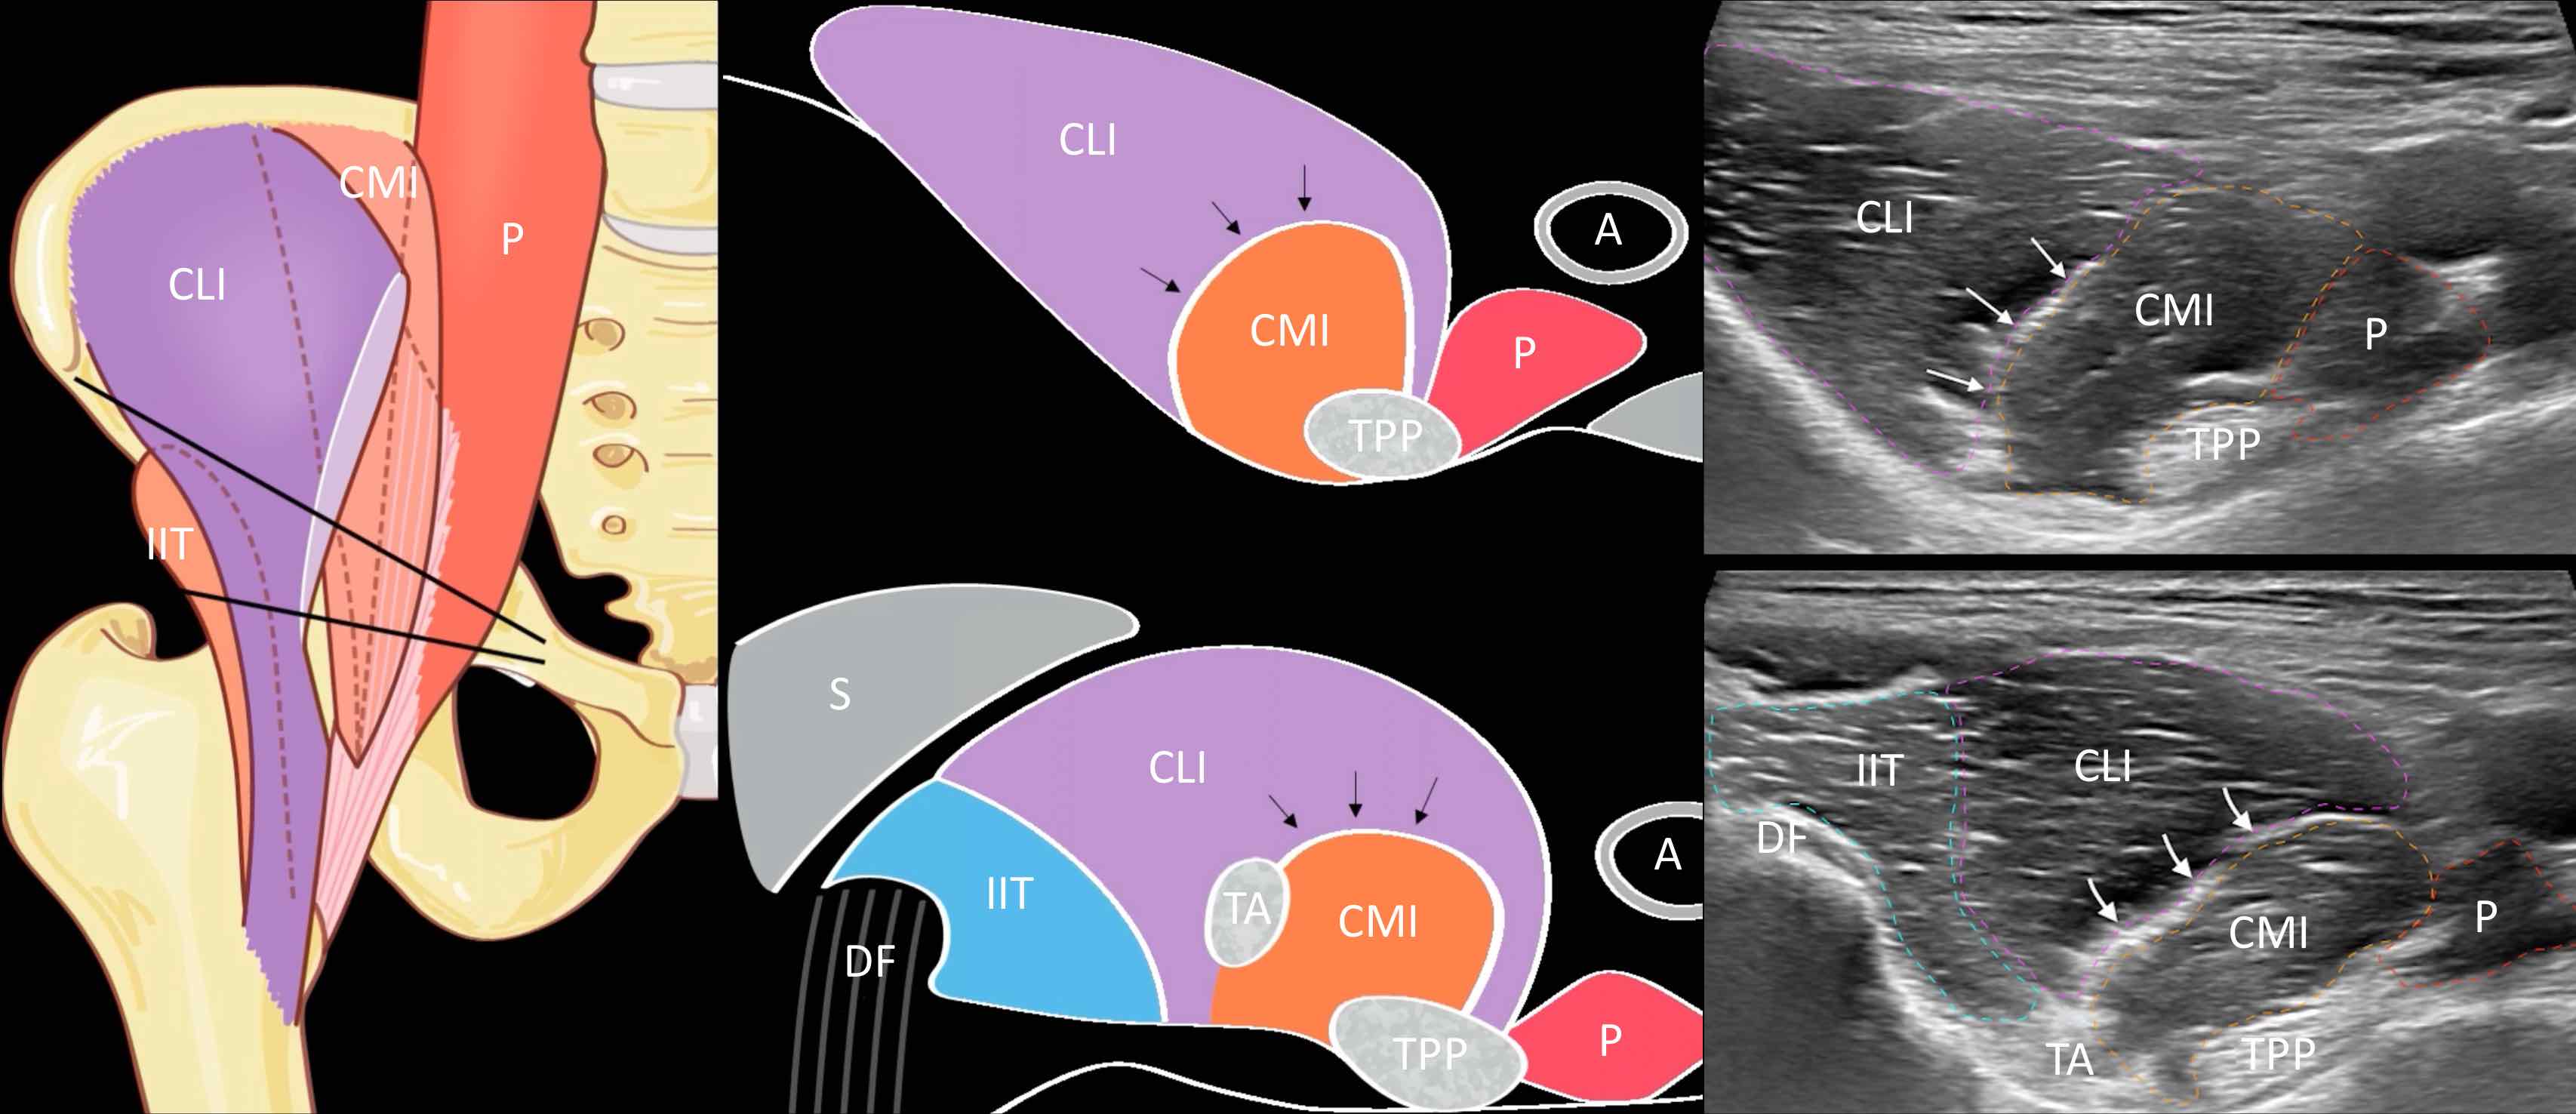

Pas d'épanchement articulaire coxo-fémoral.

Pas d'argument pour une fissure de l'enthèse du muscle long adducteur.

Pas de lésion traumatique de la jonction myotendineuse du muscle iliopsoas.

Intégrité du muscle droit fémoral et de ses insertions tendineuses.

Intégrité des tendons glutéaux et de l'insertion proximale des ischio-jambiers.

Pubalgie

Ebauches ostéophytiques péri-acétabulaires.

Pas d'épanchement coxo-fémoral abondant.

Pas de distension de la bourse ilio-pectinée.

Respect du tendon direct du muscle long fémoral.

Absence de hernie inguinale lors des manœuvres de Valsalva.

Pas d'anomalie de l'enthèse proximale des muscles adducteurs.